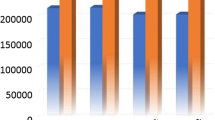

When compared to S2 (inter-ictal scan), during S1 (migraine attack scan) we found a significant reduction of thickness and volume of precentral cortex (p = 0.023 for thickness, and p = 0.018 for volume – Fig. 1) and pericalcarine cortex (p = 0.024 for thickness, and p = 0.017 for volume – Fig. 2). Also, the temporal pole cortex thickness was significantly lower at S1 when compared to S2 (p = 0.017). Regarding subcortical structures, we found an increase of hippocampus volume during S1 (p = 0.007).

Comparison of precentral cortex thickness and volume between S1 and S2 scans. Legend: S1: MRI scan performed during spontaneous migraine attack; S2: MRI scan performed during inter-ictal period; PAIN side refers to the side of spontaneous migraine attack recorded at T1. Panel A: thickness of precentral cortex was significantly lower during S1 (factor SESSION: p = 0.023), without significant association with the pain side (factor SIDE: p = 0.434, interaction SESSIONxSIDE: p = 0.515). Panel B: volume of precentral cortex was significantly lower during S1 (factor SESSION: p = 0.018), without significant association with the pain side (factor SIDE: p = 0.497, interaction SESSIONxSIDE: p = 0.276)